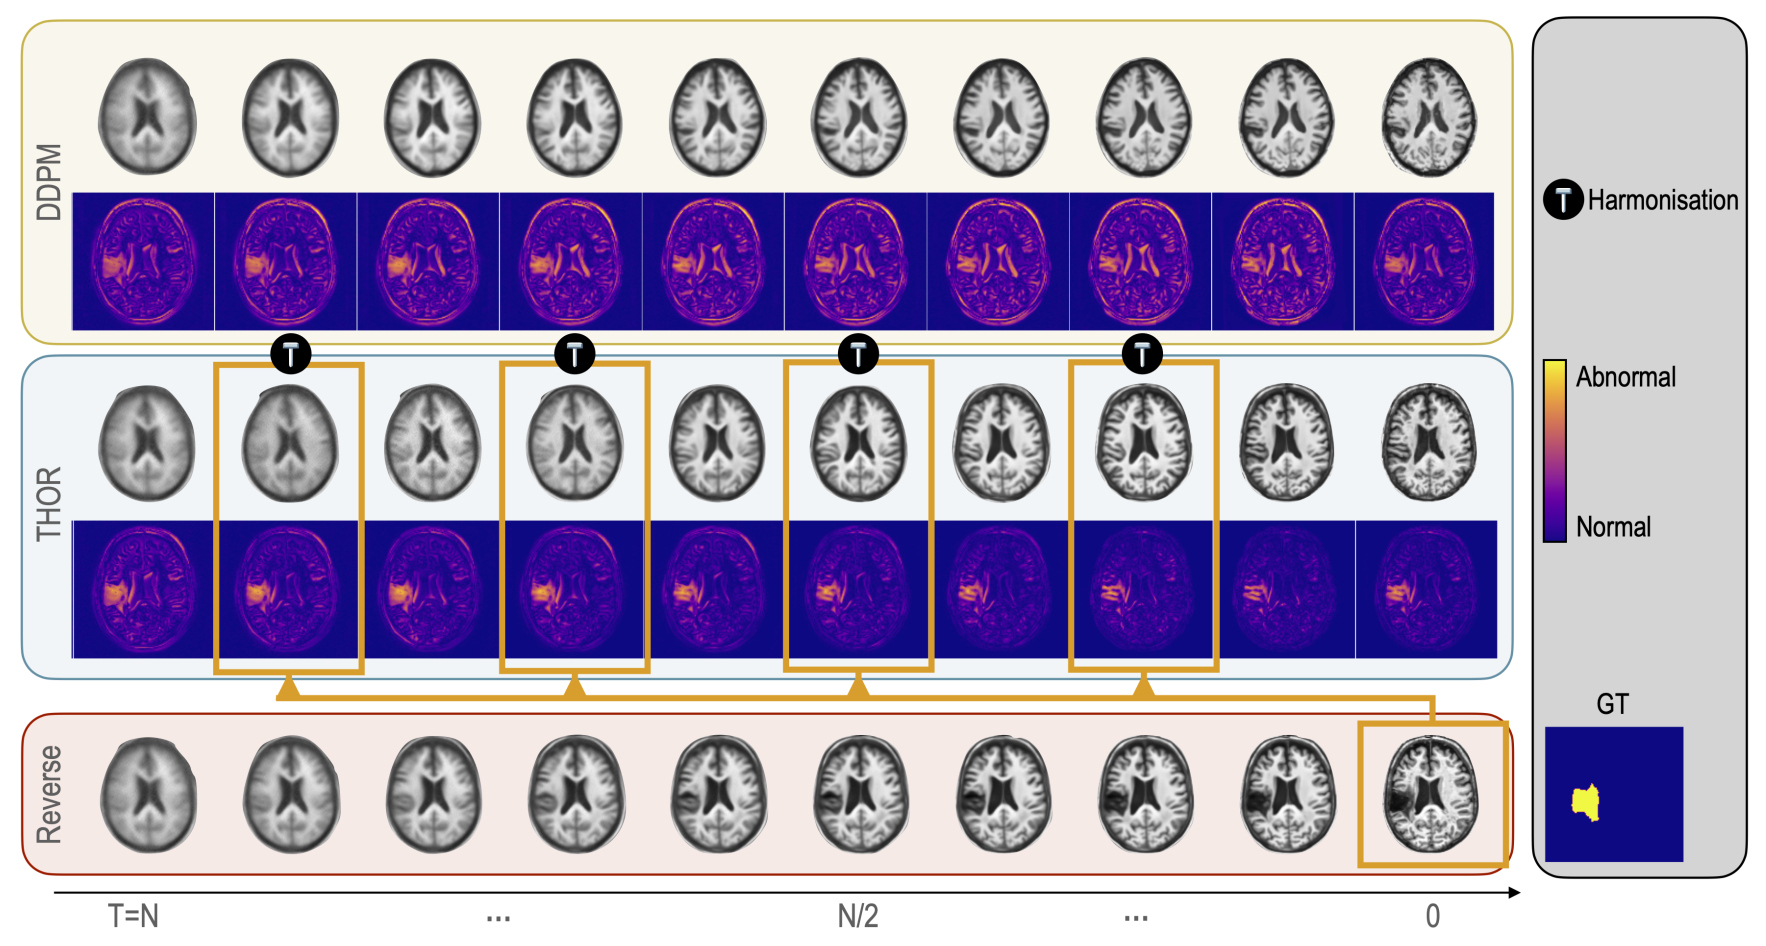

Implicit Guidance via Intermediate Anomaly Maps

Intermediate anomaly maps are introduced to enable harmonization throughout the reverse process at specific time steps

At each pre-defined specific time-step \(t\), an estimation of the pseudo-healthy image is computed as:

- These maps compare the predictive reconstructions \(\hat{x}^t_0\) with the actual input image \(x^{\text{input}}_0\), highlighting discrepancies that indicate anomalies and distinguishing regions that are likely healthy

- These anomaly maps are subsequently used in the harmonization process to produce reconstructions that not only closely resemble the original images but also conform to healthy tissue profiles

- \(\hat{x}_0\) is then used to recompute \(x_t\) following the standard diffusion process, i.e.

- The reverse process then continues until the next harmonization step

Final anomaly map

- the final anomaly map \(S\) is computed using the harmonic mean of the anomaly maps at the selected timesteps, defined as

\(\displaystyle S = n \, \Big/ \, {\sum_{t \in \text{selected steps}} \frac{1}{m(\hat{x}^t_0,x^{\text{input}}_0)}}\)

where \(n\) is the total number of selected harmonization timesteps